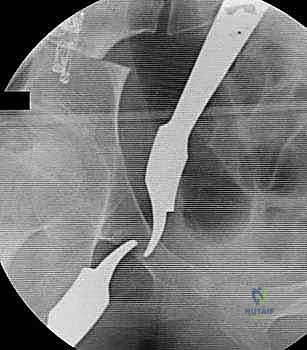

باستخدام أدوات خاصة، يقوم الدكتور هطيف بتدوير التجويف الحقي الحر في ثلاثة أبعاد (للأمام، وللخارج، وللأسفل) حتى يغطي رأس عظم الفخذ بشكل مثالي وميكانيكي سليم. يتم التحقق من الزاوية الجديدة فوراً داخل غرفة العمليات باستخدام جهاز الأشعة السينية المتحرك (C-arm).

5. التثبيت القوي (Fixation)

بمجرد الوصول إلى الوضع المثالي، يتم تثبيت العظام في مكانها الجديد باستخدام براغي معدنية قوية من التيتانيوم أو دبابيس (K-wires). هذا التثبيت يضمن التحام العظام بشكل صحيح خلال فترة التعافي.